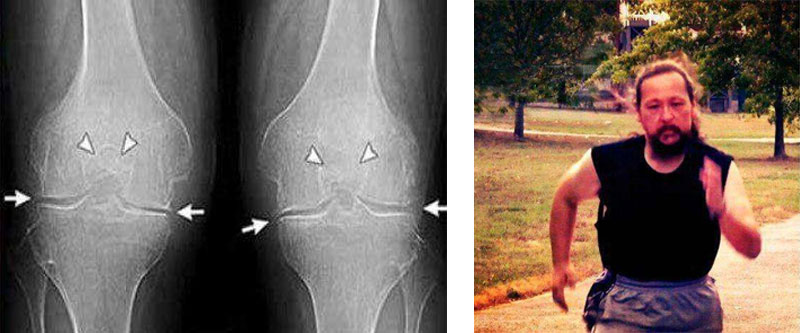

Εμένα το Turmeric Curcumin με βοήθησε πολύ! Πρήστηκε το γόνατο δεν μπορούσα

να λυγίσω

το πόδι μου. Ο πατέρας μου μου έφερε από κάπου το και Turmeric Curcumin Δόξα το Θεό! Δείτε την

διαφορά:

πόδι μου. Ο πατέρας μου μου έφερε από κάπου το και Turmeric Curcumin Δόξα το Θεό! Δείτε την διαφορά:

Εμένα το Turmeric Curcumin με βοήθησε πολύ! Πρήστηκε το γόνατο δεν μπορούσα να λυγίσω το πόδι μου. Ο πατέρας μου μου έφερε από κάπου το και Turmeric Curcumin Δόξα το Θεό! Δείτε την διαφορά: